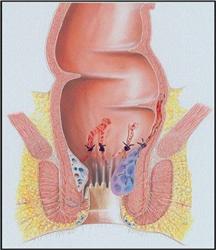

Haemorrhoids

Haemorrhoids (also known as piles) are a common ailment, caused by the enlargement and congestion of the superficial veins in or around the rectum and anus. Those occurring around the anus are called external haemorrhoids, those that occur in the rectum are called internal haemorrhoids, and if the external and internal haemorrhoids occur at the same time, they are called mixed haemorrhoids.

Haemorrhoids (also known as piles) are a common ailment, caused by the enlargement and congestion of the superficial veins in or around the rectum and anus. Those occurring around the anus are called external haemorrhoids, those that occur in the rectum are called internal haemorrhoids, and if the external and internal haemorrhoids occur at the same time, they are called mixed haemorrhoids.Habitual constipation is thought to be the most important risk factor causing haemorrhoids. Excessive force for excretion of faeces can put pressure on the veins in and around the anus, making them inflamed and swollen. Other risk factors include: being overweight, pregnancy and childbirth, prolonged diarrhoea, enlarged prostate causing difficulty in urination, lifting heavy objects, prolonged sitting or standing, as well as long distance walking. These cause the increase of pressure in the abdominal cavity, thus the blood flow in the veins returning to the heart will be blocked and cause varix, which will finally lead to the formation of haemorrhoids.

Some people with haemorrhoids may experience no symptoms. Common symptoms for haemorrhoids include bleeding or/and a mucus discharge after passing a stool, pain and itchiness around the anus, rectal prolapse of various degrees, and feeling that the bowels are not fully emptied. Patients with these symptoms must get a clear diagnosis by going through an anoscopy or sigmoidoscopy to rule out the possibilities of bowels cancer, colitis and polyp of the rectum.

Treating haemorrhoids with Traditional Chinese Medicine may achieve very good results. It can improve the blood circulation, diminish inflammation, relieve pain, and stop bleeding.